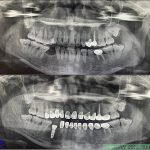

Ca này không phải răng khôn mà là răng 6 hàm trên, có lỗ sâu mặt trong không để ý xử lý kịp thời, dẫn tới hậu quả mất răng và phải cắm Implant khá tốn kém.

Ca này nếu thời điểm bây giờ thì tôi sẽ tư vấn nhổ và cấy implant tức thì luôn trong 1 lần để giảm thời gian chờ đợi cho bệnh nhân.